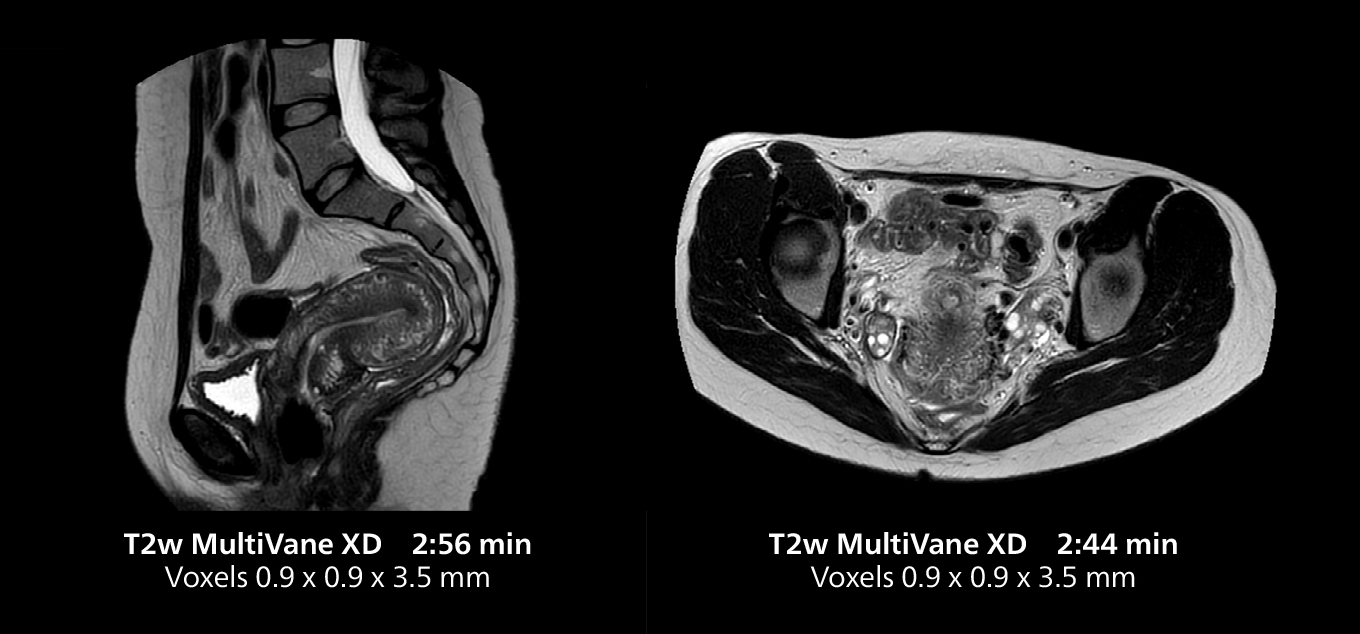

This MRI case illustrates good resolution and imaging quality obtained within reasonable scan times using the MR 5300 1.5T system with the anterior torso cardiac coil that allows use of a large field of view (FOV).

Dr. Gellée highlights the robust free-breathing scans as “the feature that makes the biggest difference in my daily work. The 3D free breathing sequences are very reproducible, and the axial acquisition is very good. For example, in endometriosis, which is one of my focus areas, it provides high contrast and good resolution so that I can see small details. We also use free breathing for liver and pancreas imaging. In multi-phase liver studies, 4D Free Breathing delivers 3-second temporal resolution, making a dynamic scan with more than one arterial phase possible.”